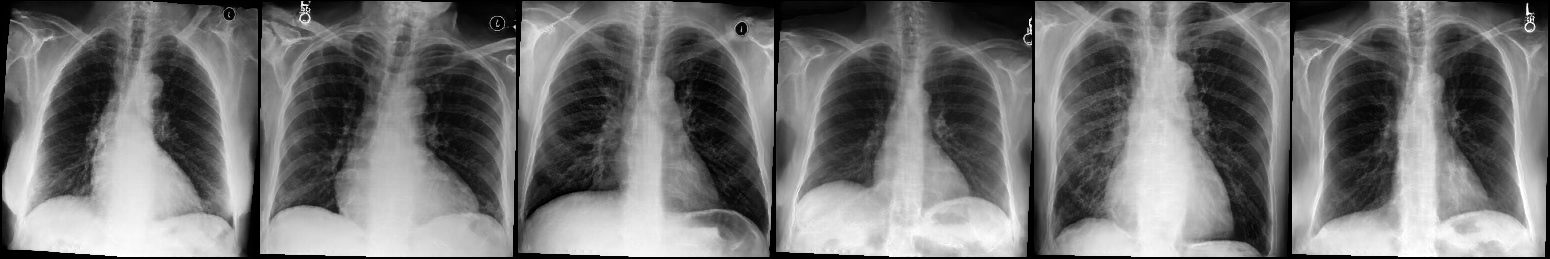

Image Reconstruction. Table 1 shows that the co-training scheme outperforms the \mathcal{E}-training approach in reconstruction accuracy, as indicated by higher PSNR and IW_SSIM scores, highlighting the benefits of joint optimization for enhancing reconstruction quality. The results are further validated by the visual comparison in Fig. 2, where the co-training scheme recovers input images with finer details and higher fidelity. In contrast, the \mathcal{E}-training scheme exhibits noticeable discrepancies when compared to the original images.

Refer to caption

XRX_{R}

Co-training

\mathcal{E}-training

Fig. 2: Reconstruction results. The first row displays the real images XRX_{R}. The last two rows show the reconstructed images X^R\hat{X}_{R} produced by the proposed co-training scheme and the \mathcal{E}-training scheme, respectively.